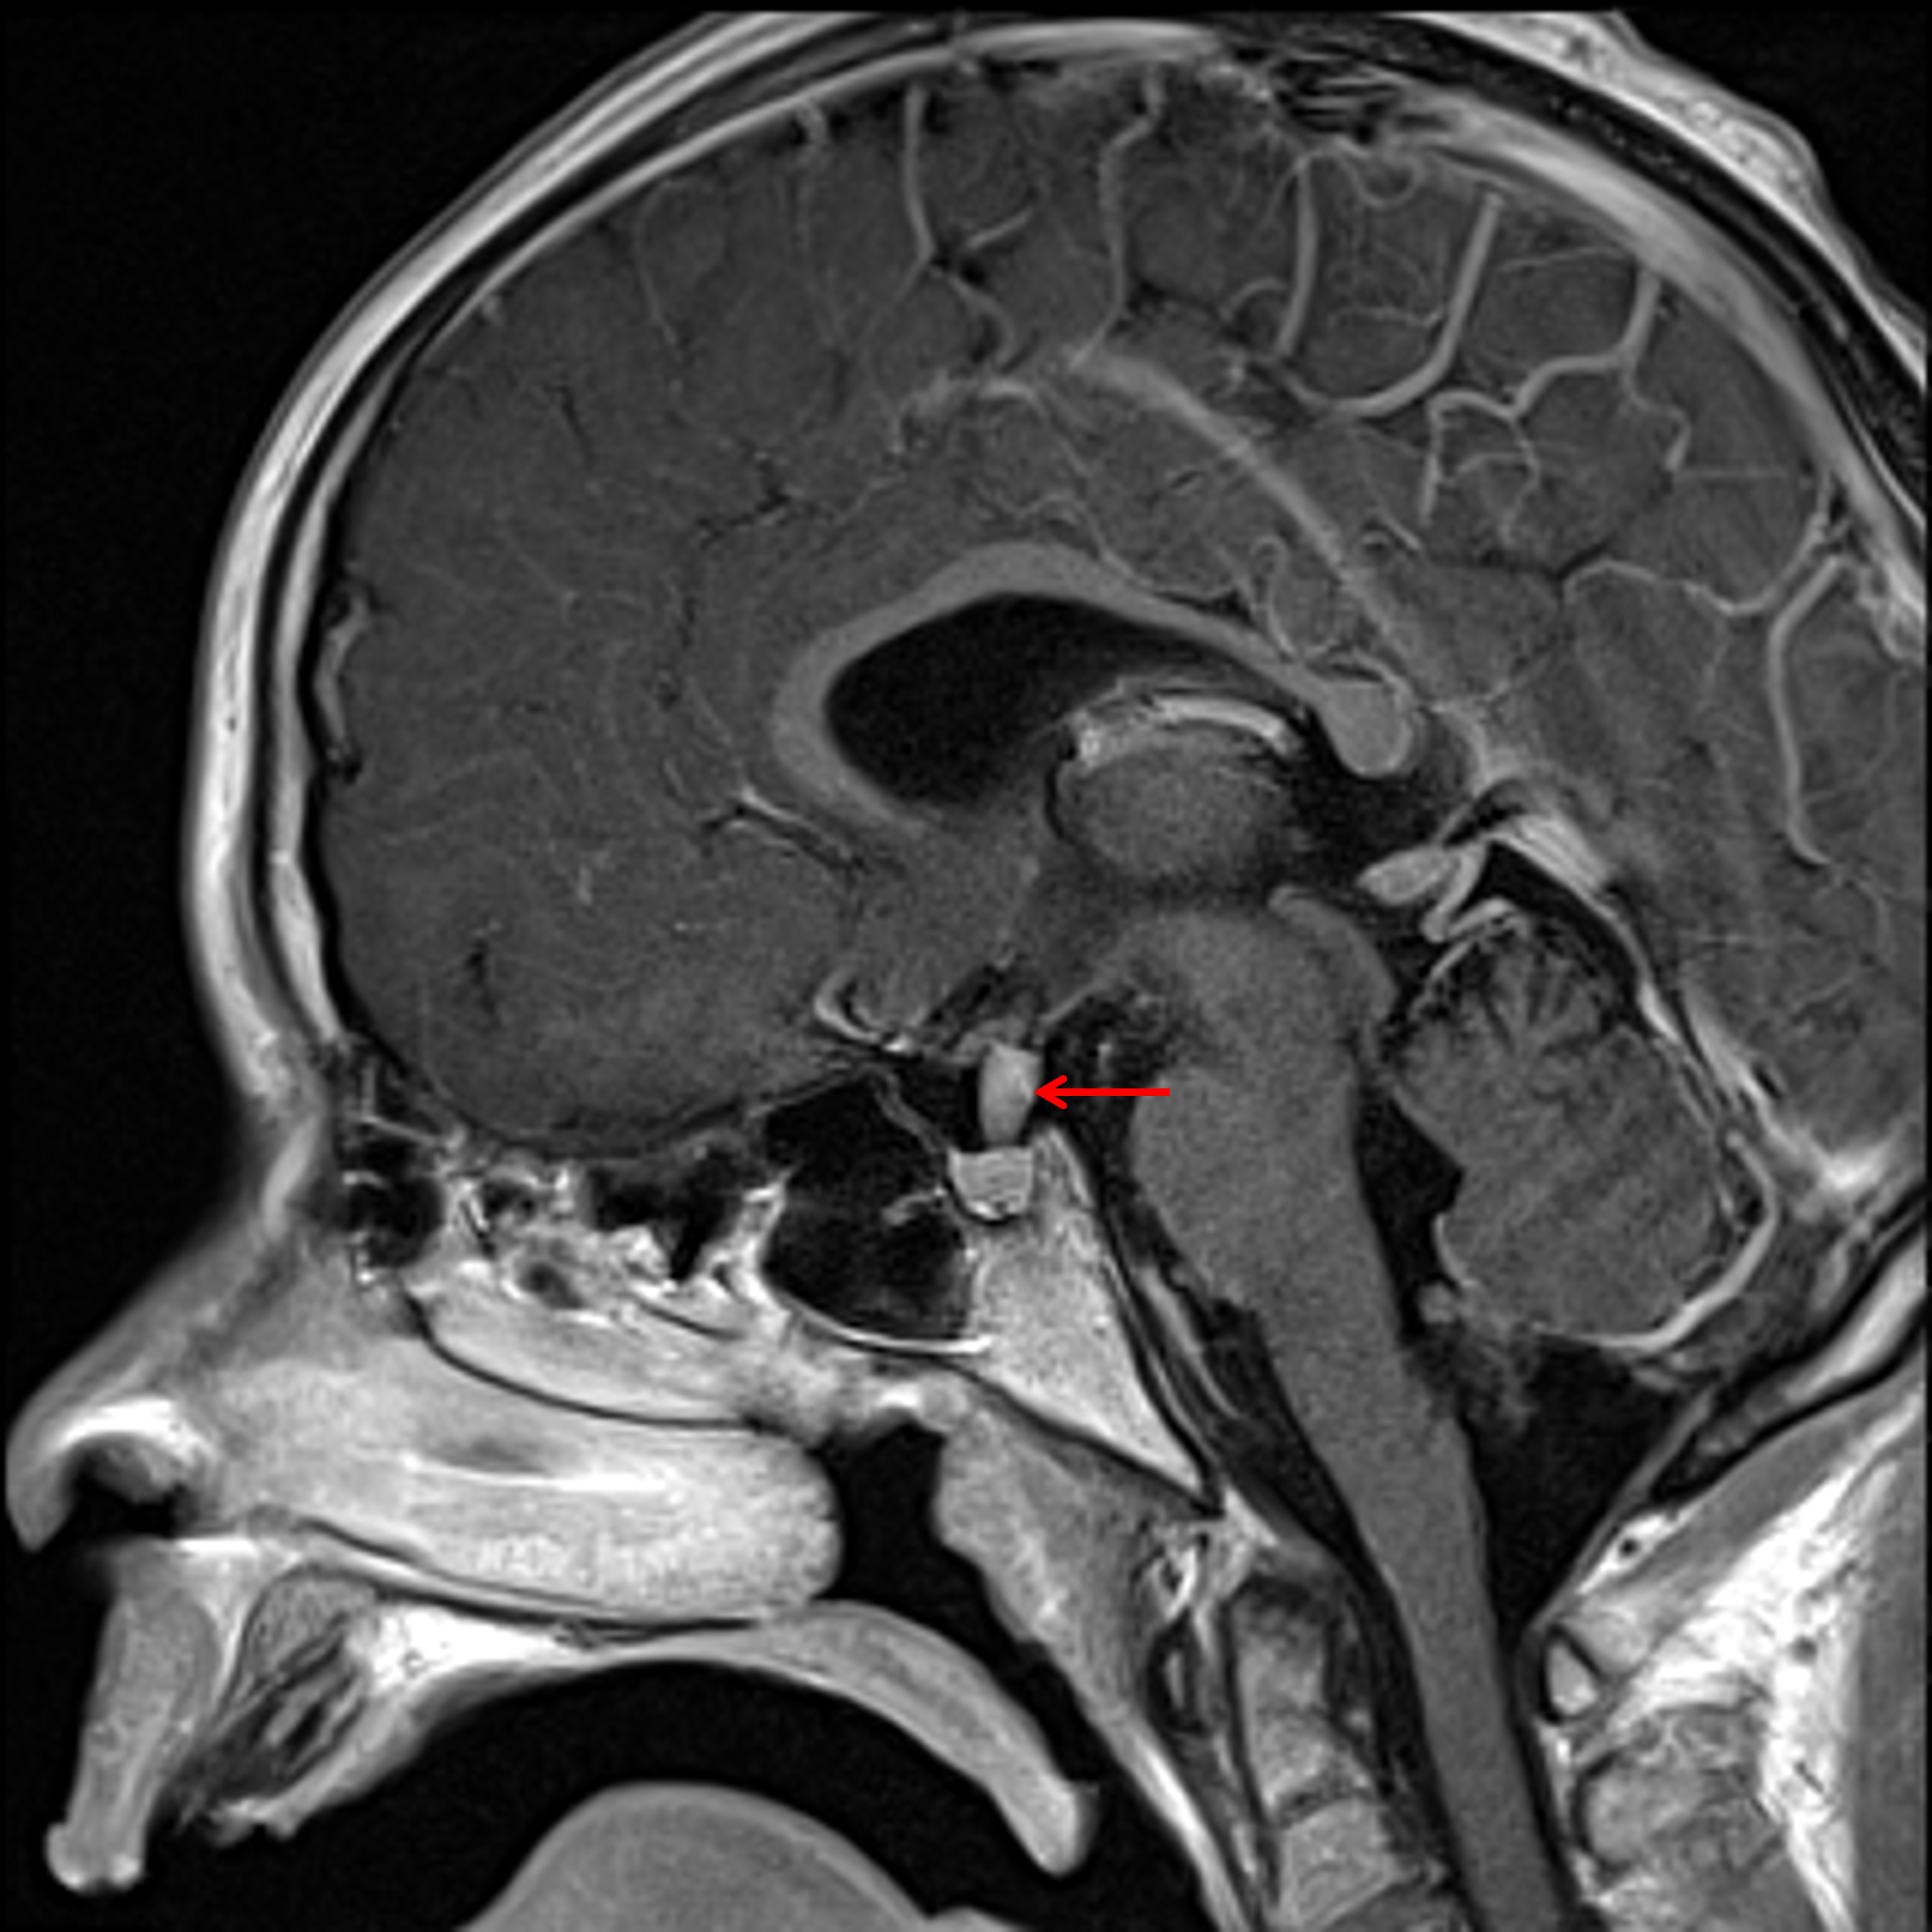

Age: 11

Sex: Male

Indication: Diabetes insipidus

Langerhans cell histiocytosis (LCH)